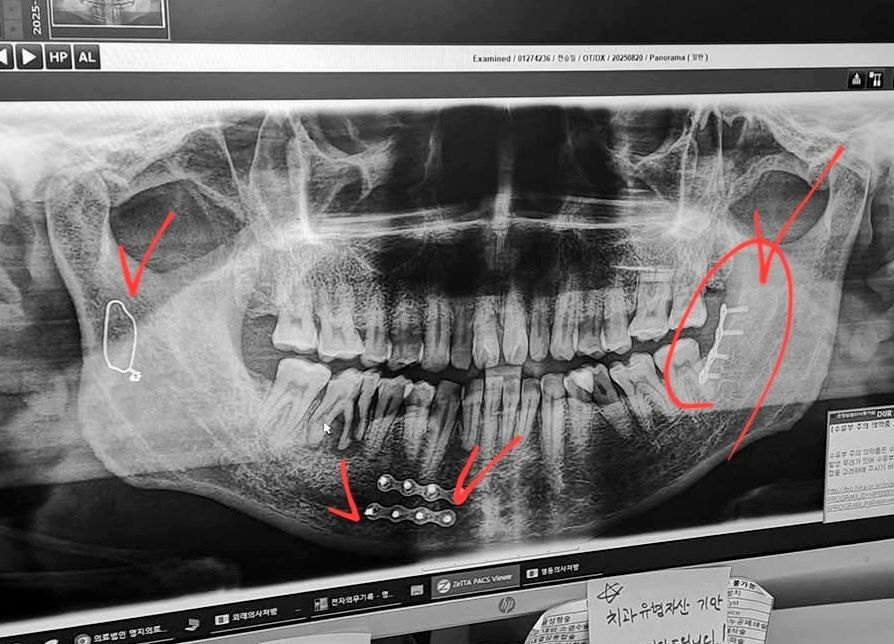

2024년 11월에 오른쪽눈 인공수정체가 탈구되어 힘들게 망막 수술(유리체절제술, 망막박리술, 탈구인공수정체제거, 공막고정술)을 했고, 2025년 1월에 왼쪽눈도 수정체 교체 수술을 했습니다. 그런데 그후에도 계속 안면 통증과 두통이 더 심해지고, 하악통증, 척추와 가슴통증 등으로 번지고 있어서 매우 힘든 상황이 이어지고 있습니다.

현재 고양시 명지병원과 동국대일산병원 안과, 신경과, 치과, 이비인후과, 신경외과, 정형외과, 심장내과, 류마티스 내과 및 통증의학병원을 다니고 있습니다. 가정의학쪽의 소견은 자율신경계의 심각한 손상으로 인한 난치성 만성 통증이라고 하는데, 아직도 정확한 치료 방향을 찾지 못하고 있습니다. 뇌MRA 결과 뇌신경계 혈관에 문제가 있으니 뇌혈관 조영술로 정밀검사를 받으라고 합니다.

그리고 대학 시절 학과 선배의 일방적인 가격 폭행으로 하악 골절 4곳이 부러지는 심각한 부상을 입고 장기입원을 하며 큰 수술을 2번 했는데, 이로 인한 턱관절 장애 고통와 안면통증도 심각합니다. 지금도 하악 4곳에 보철이 들어 있고, 하악관절 장애 진단이 나왔습니다. 통증이 심해서 음식을 제대로 먹지 못하기 때문에 전반적인 몸상태가 매우 좋지 않습니다.